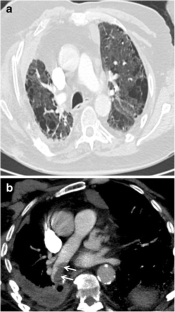

Fig. 1